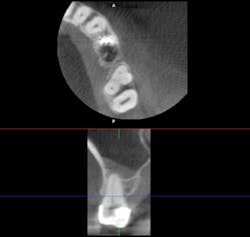

The old saying “you don’t know what you don't know” holds especially true in regard to 3-D radiology. You simply cannot gain the same amount of information from 2-D images. My main use for CBCT in the general dentistry practice is dental implant planning. In order to feel confident placing dental implants, I need this technology. I am able to identify cases that are appropriate for my skill level, as well as cases that are more difficult and should be referred. Whether a case will be tricky is not always obvious from a 2-D image and clinical exam. I also have not found a situation where less information was more beneficial than more information. I have never thought to myself, “I wish I didn’t have a 3-D scan of this patient.” Conversely, there were many times before buying my CBCT when I wished I had more than just a 2-D periapical (PA) or pan. The case shown in figures 1, 2, and 3 illustrates how the additional information CBCT provides aids in planning and placing dental implants.

Figure 3 tells a more complete story. The patient has a significant lingual concavity. I was unable to palpate the concavity clinically to realize its full extent. The 3-D image allows accurate measurement to the inferior alveolar nerve (IAN) and lingual concavity. It allows me to plan and place an implant of the appropriate length to avoid perforation of the lingual plate, which could lead to serious surgical complications.